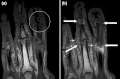

(a) STIR Sagittal MRI of ankle showing enthesitis at Achilles tendon insertion (thick arrow), synovitis of ankle joint (long thin arrow), and bone marrow edema at tendon insertion (short thin arrow). T1-weighted images, before (b) and after (c) contrast, show enthesitis (large arrow) and bone erosion at tendon insertion (short thin arrows).